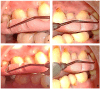

Background: Antimicrobial Photodynamic therapy for the treatment of periodontitis is being increasingly gaining attention but at present, very limited data are available on the clinical and microbiological outcomes obtained following Indocyanine Green as the photosensitizer in Maintenance patients. The objective was to evaluate the efficiency of Indocyanine(ICG)-green based photodynamic therapy as an adjunct to scaling and root planing in patients enrolled in maintenance therapy. Methodology: Using a split mouth study design, 24 participants enrolled in the maintenance therapy, having diagnosed as Periodontitis, were randomly subjected to scaling and root planing(SRP). The test group additionally received ICG-based (Aurogreen ®, Aurolabs, Madurai, India,1mg/ml) aPDT with an 810nm diode laser. Clinical assessment of Plaque index, modified Sulcus bleeding index, Probing pocket depth, Clinical loss of attachment and microbiological analysis of A. actinomycetemcomitans, P. gingivalis, T. forsythia and F.nucleatum were performed at baseline and 3 months after treatment. Results: It was observed that although there was no significant difference between the test and control group at baseline and 3 months, there was a statistically significant reduction in the mean values in both the groups at 3 months. Microbiological analysis showed substantial reduction in detection frequency of the bacteria assessed at 3 months in both the groups. Conclusion: Within the limits of the study, ICG-based aPDT did not show additional advantage over SRP alone at 3 months, though it could be a promising treatment modality in maintenance patients in terms of patient comfort and the treatment time taken. More randomised clinical trials should be employed to understand the exact mode of action of ICG based aPDT and its role in treatment of periodontal disease.